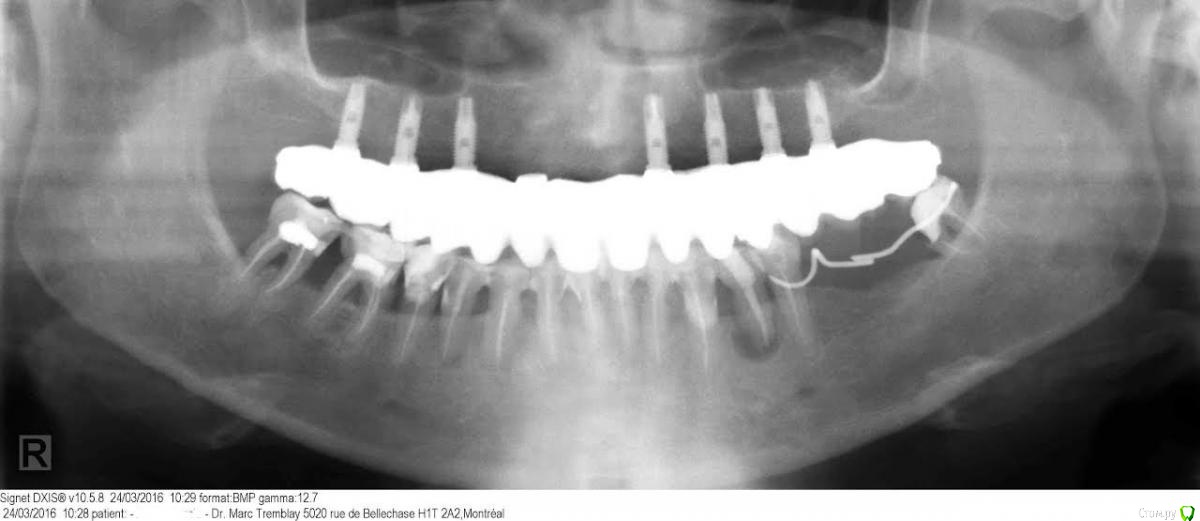

Zoia Опубликовано 22 сентября, 2016 Поделиться Опубликовано 22 сентября, 2016 Здравствуйте, уважаемые доктора! Очень нужно ваше мнение. История такая: 1- в октябре 2007 года -наращивание костной ткани на верхней челюсти с использованием кости взятой у меня.2- апрель 2008 - имплантация, 8 имплантов3- декабрь 2008 - протезирование.Несъемный мостовидный протез -цирконий.4- март 2009 - воспаление тканей возле 12-го импланта, лечение антибиотиками.5- март 2011 - воспаление тканей возле 12-го импланта, сняли протез, обработали все импланты перидексом, и назначили антибиотики.6- февраль 2016 -флюс возле 12-го импланта, доктор, когда стал снимать протез, сказал, что 12-й имплант проворачивается в кости, поэтому не получается отвинтить протез, и что он вытащит имплант. Вытаскивать его было очень больно, пришлось 2 раза делать анестезию. Обработали все импланты зонитом и перидексом.7-март 2016 - увеличение альвеолярного гребня на месте 12-го импланта с использование гранул. Врач предлагает снова поставить имплант на место выпавшего. Как вы думаете, стоит ли это делать? Что может случиться, если не делать реимплантацию? Что более рискованно для меня? Мне 59 лет.Снимок прилагается. Подскажите, пожалуйста. Ссылка на комментарий